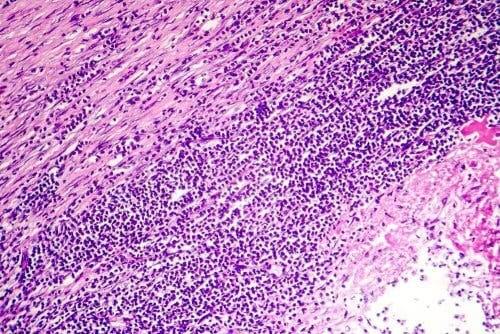

Det er umuligt at fastslå årsagen til pericarditis i ca. 80% af tilfældene. Det er dog meget almindeligt, at dets oprindelse er resultatet af en slags infektion. Det er meget sandsynligt, at det er en virusinfektion. Der kan være en bakterieinfektion, men i sjældnere grad, og kun meget sjældent kan det skyldes en svampeinfektion.